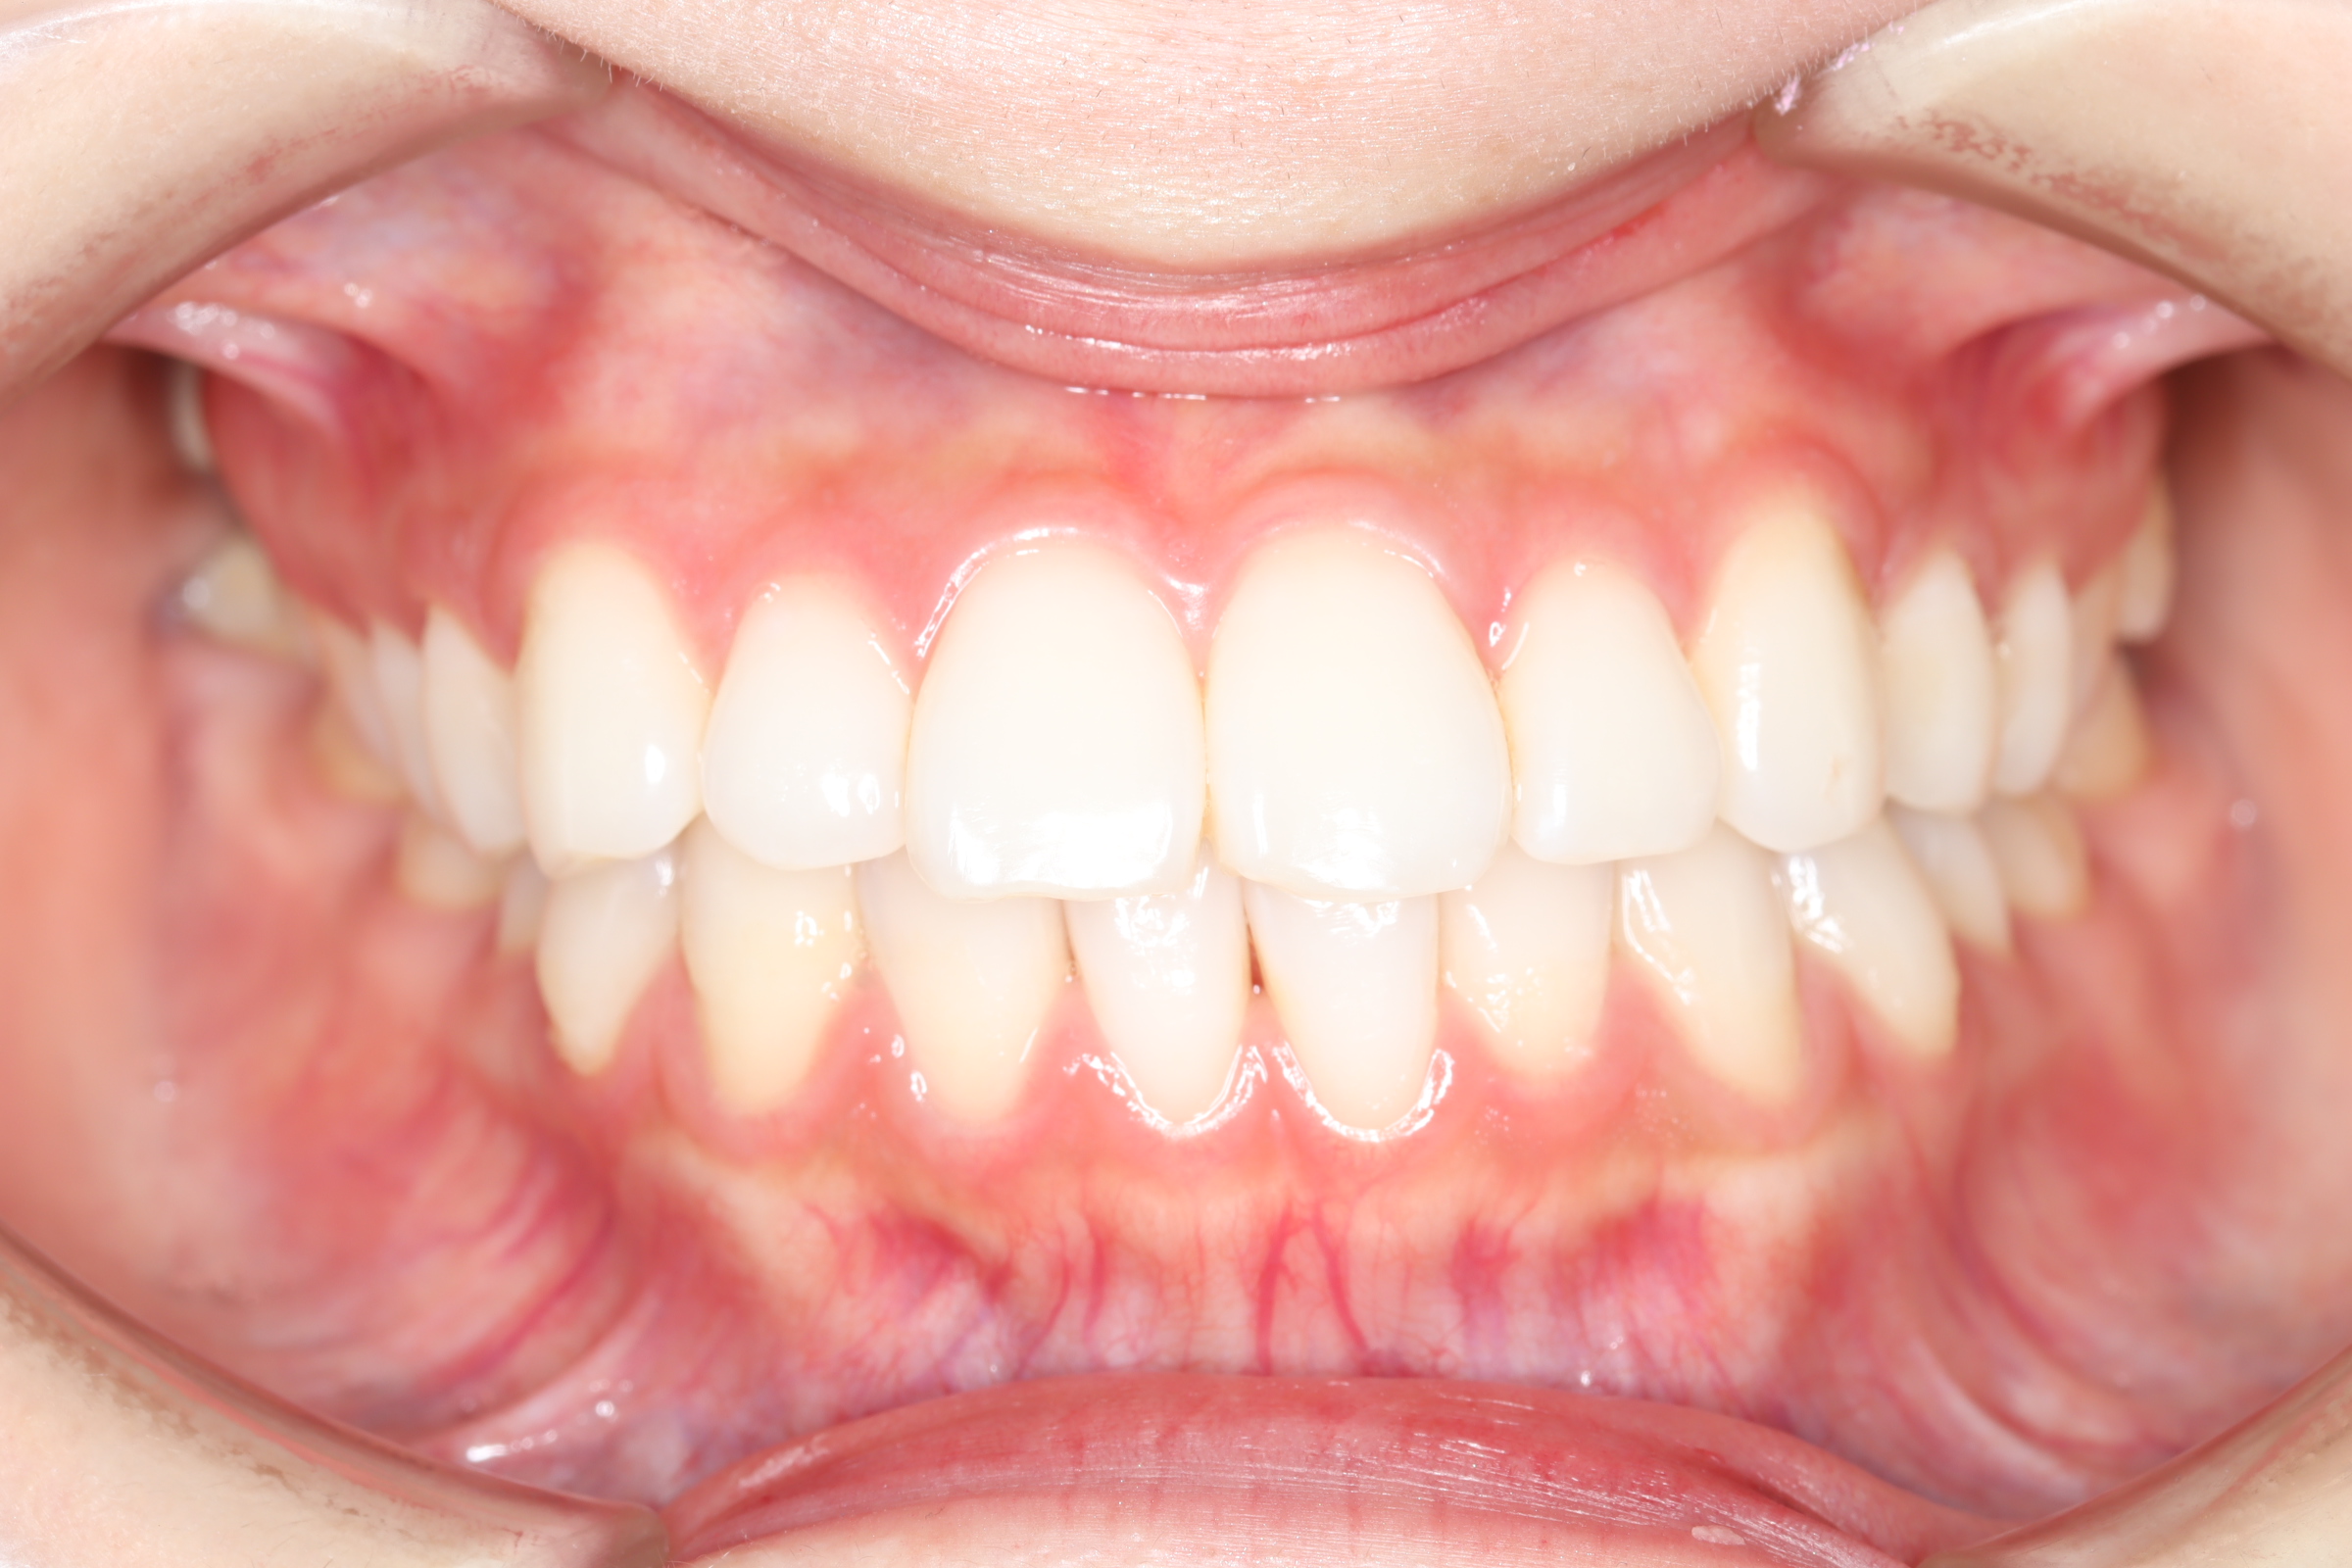

口腔内とラテラルセファログラムの変化

![]() | ![]() | ![]() |

| ↓ | ↓ | ↓ |

| 治療後 | 前歯から奥歯まで全体的に緊密な咬み合わせになっています。 治療前後のセファログラムのトレースの重ね合わせを比較すると、上下の歯列の後方移動ができ、それにより口元もよりすっきりしました。 また前歯の唇側傾斜も改善されています。 |